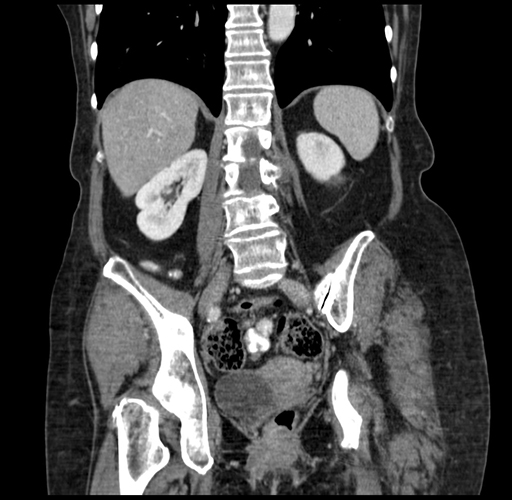

Pre-Chemo: Coronal Venous